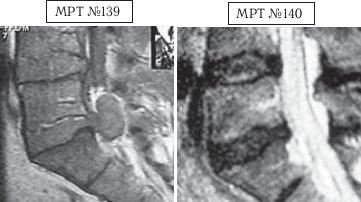

На МРТ № 139 — состояние поясничного отдела позвоночника: рецидив грыжи межпозвонкового диска после хирургической операции. Наблюдается абсолютный стеноз спинномозгового канала, грыжа межпозвонкового диска в сегменте LV-SI , осложнённая массивным секвестром с его миграцией как в каудальном (вниз), так и в краниальном (вверх) направлении. Размер грыжи дорсально — до 14,5 мм, каудально-краниально — до 26,8 мм.

На МРТ № 140 наблюдается состояние поясничного отдела позвоночника после лечения методом вертеброревитологии: отсутствие грыжи межпозвонкового диска в сегменте LV-SI , отсутствие стеноза позвоночного канала.